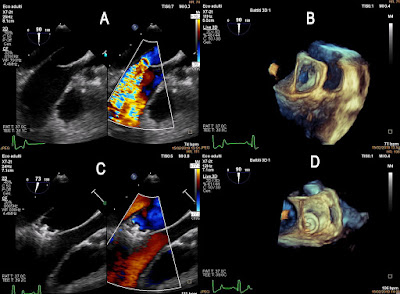

Studio ecocardiografico transesofageo bidimensionale e tridimensionale eseguito durante una procedura interventistica di chiusura di PDA.

Nelle figure A e C potete osservare le immagini bidimensionali del dotto arterioso prima e dopo il posizionamento del dispositivo mentre nelle figure B e D il dotto viene studiato con ecocardiografia tridimensionale. Questa tecnica permette una maggiore precisione nello studio delle dimensioni e della morfologia del dotto e di conseguenza nella realizzazione dell'intervento.